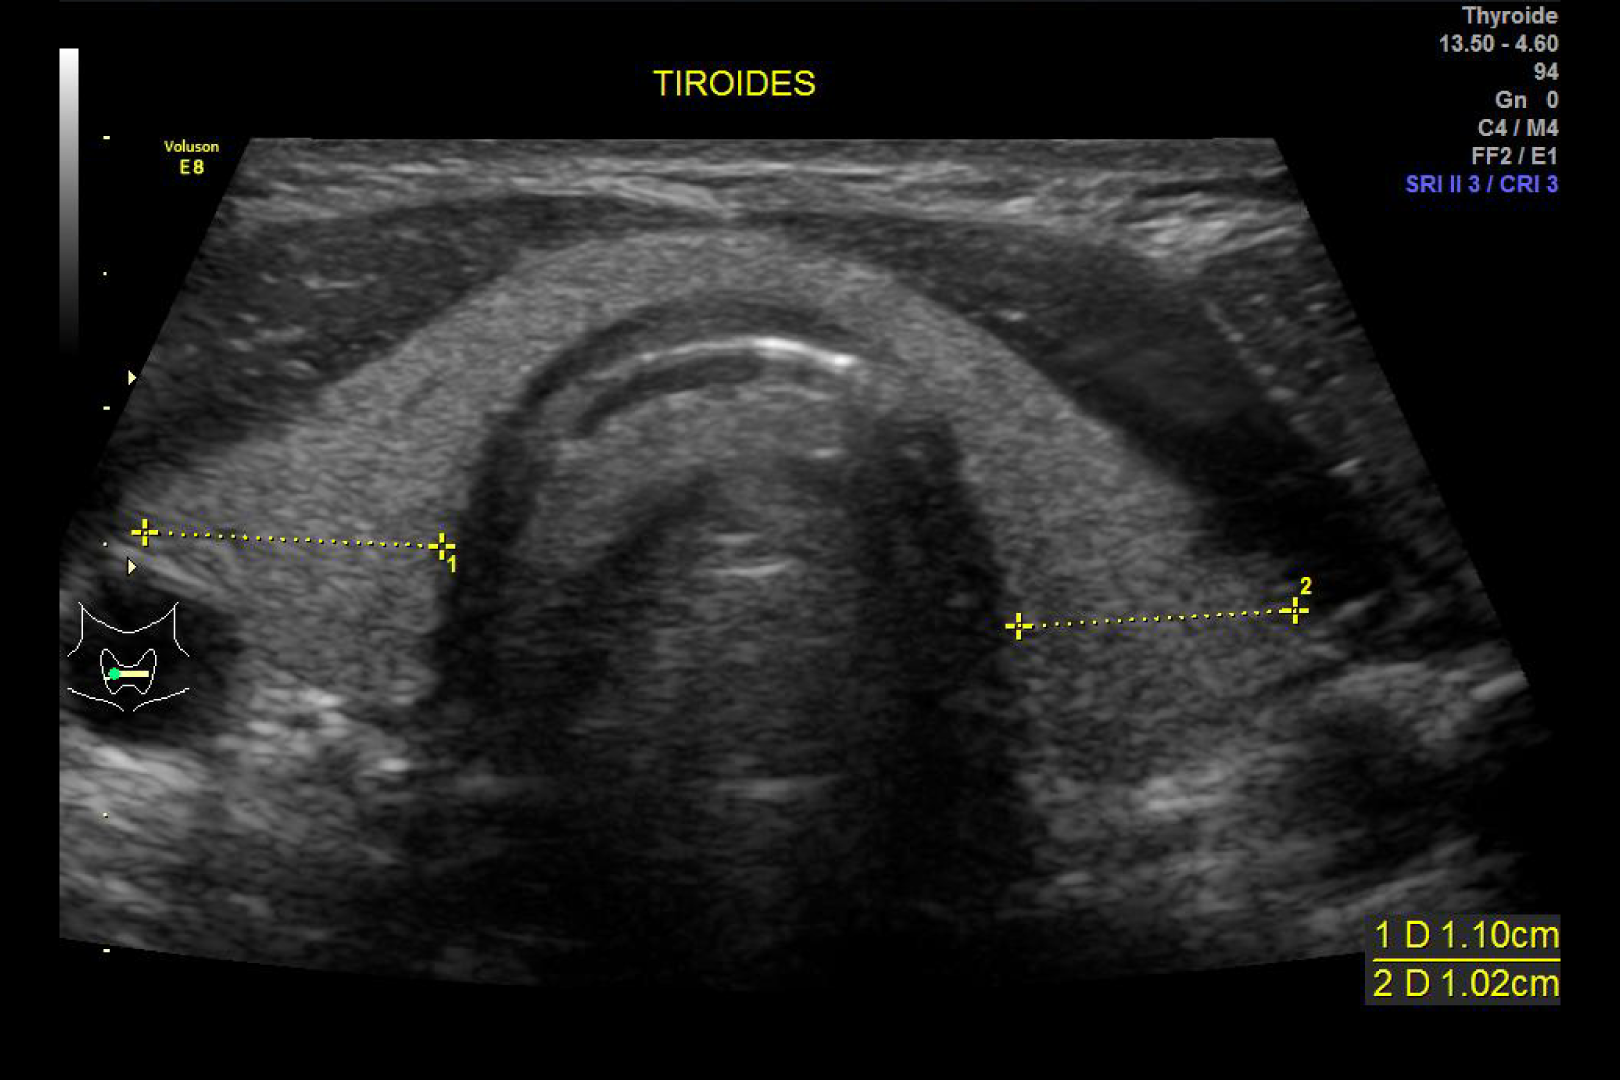

HD Live quinta dimensión, Imágenes de volumen con profundidad y claridad, que aportan un realismo anatómico para un mejor diagnóstico.